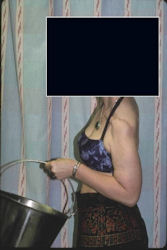

Examples of radical limb sparing surgeries for osteosarcomas in various anatomic locations (distal femur, proximal tibia, proximal humerus, scapula)

In each case, the tumor and bone from which it arose were resected. This required meticulous dissection, mobilization and preservation of adjacent pertinent neurovascular structures. In each case presented here, the defect was reconstructed with a special modular segmental tumor prosthesis. This also replaces the adjacent joint in many instances.

Proximal Humerus: Radical Limb Sparing Extra-Articular Resection and Prosethetic Reconstruction